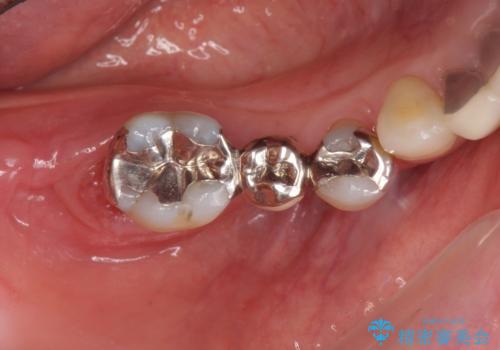

- 歯周病で失った奥歯や、グラグラしている歯の治療を希望され来院されました。

残すことのできない歯を抜去したのち、骨を造成し安定した環境下で長期的な予後を期待できるインプラント治療を計画します。